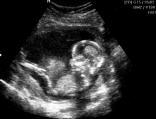

Schwangerschaft und Nabelschnurblut

HERZLICHEN GLÜCKWUNSCH ZUR SCHWANGERSCHAFT!